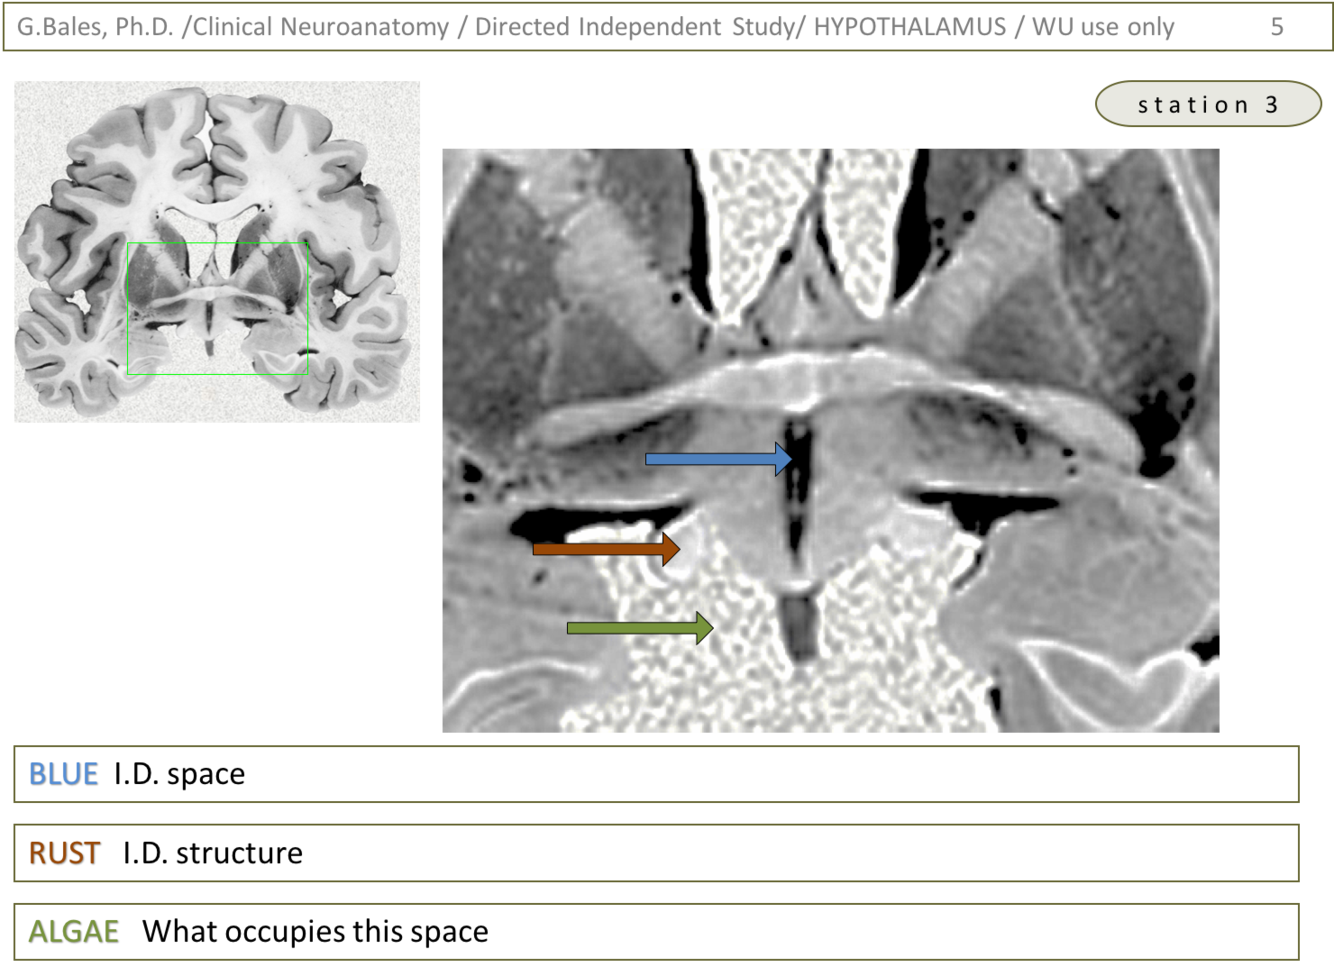

1) Blue – 3rd ventricle (Hypothalamus lecture – slide 10)

2) Rust – fairly certain it is the optic tract (Reference this website: http://www.neuroanatomy.ca/cross_sections/sections_coronal.html)

Algae – this space will eventually be occupied by the pons (Reference this website: http://www.neuroanatomy.ca/cross_sections/sections_coronal.html